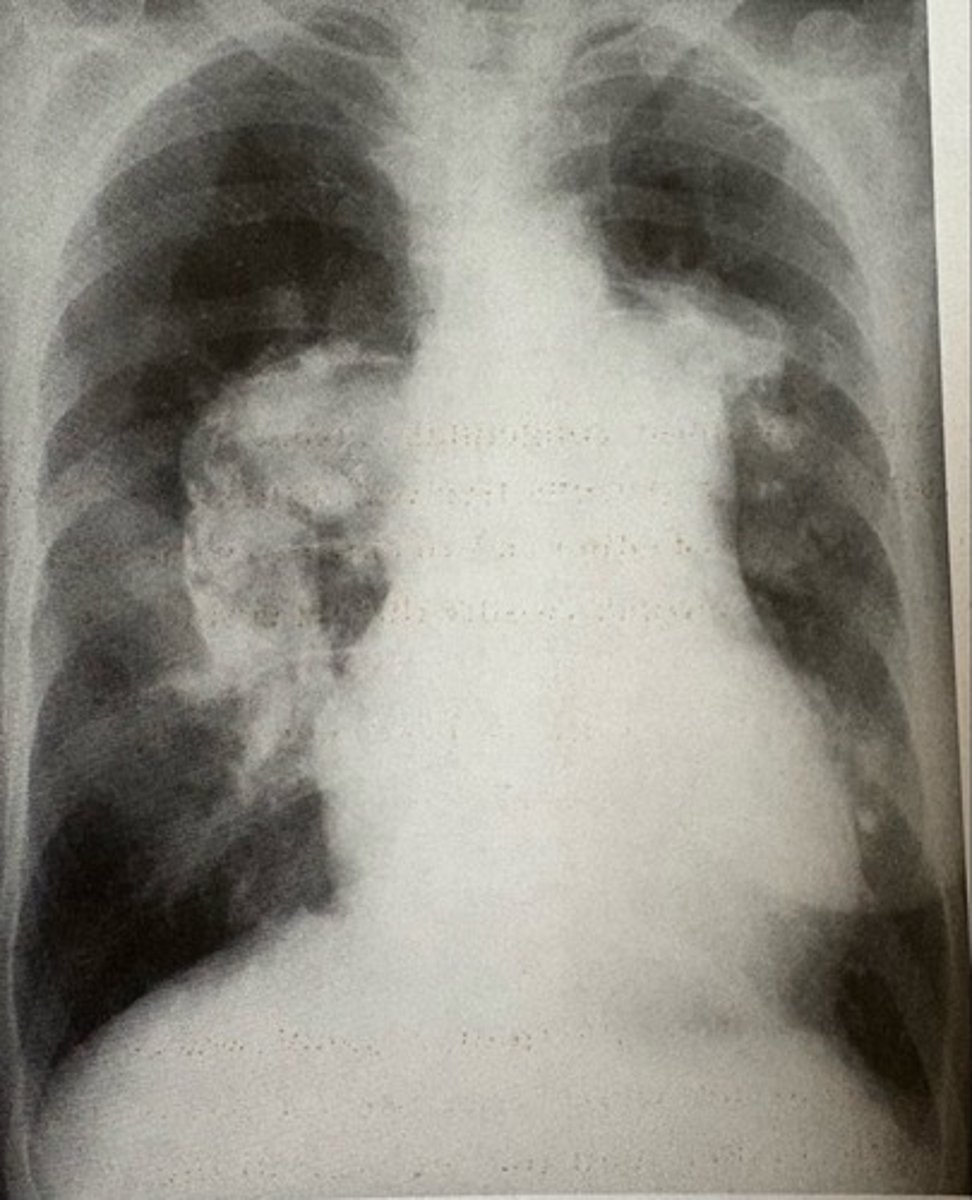

Eisenmenger Syndrome and atrial septal defect

what pathology is present?